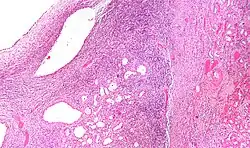

Micrograph of a cystic nephroma (left of image). Normal kidney is seen on the right. H&E stain. | |

The characteristics of cystic nephromas are:

- Cysts lined by a simple epithelium with a hobnail morphology, i.e. the nuclei of the cyst lining epithelium bulges into the lumen of the cysts,

- Ovarian-like stroma that has a:

- Spindle cell morphology, and has a

- Basophilic cytoplasm.